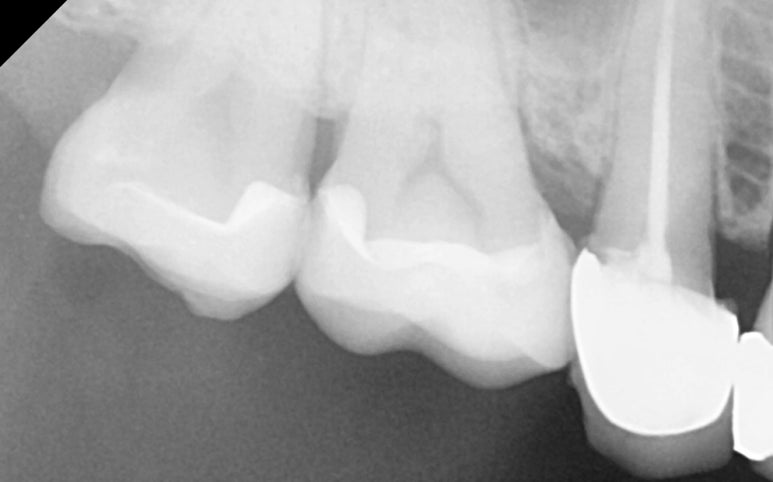

25.11.11 레진 코팅 후 엑스레이 사진

레진 코팅(Resin Coating)

본을 뜨기 전, 노출된 상아질을

레진으로 얇게 코팅하여 신경을 보호하고

접착력을 극대화합니다.

이 과정을 거치면 치료 후 시린 증상이 현저히 줄어듭니다.